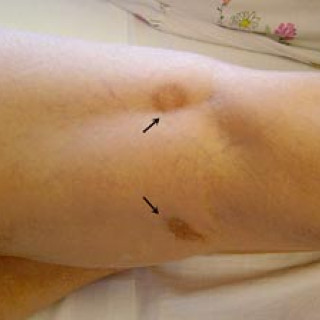

En 52 år gammel etnisk norsk mann ble innlagt i psykiatrisk akuttavdeling etter noen få uker med kraftig økende aktivitetsnivå. Han hadde vist markant endret atferd – blant annet hadde han satt seg fore å sykle åtte mil i kuldegrader og slaps. Ved innleggelsen var han irritabel og snakket fort og nærmest usammenhengende. Somatisk status presens ved innkomst samt orienterende nevrologisk status var normale. Vanlige blodprøver ved innleggelse, inklusive Hb, SR, hvite blodceller, kreatinin, natrium, kalium, ALAT, ASAT, ferritin, folat, kobalamin, FT4, TSH, var alle innenfor referanseområdet...